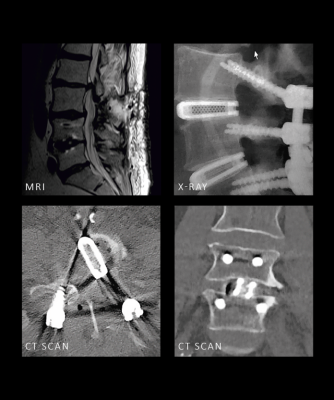

Optimal Visualization

JULIET®Ti cages are designed for reduced overall density to optimize imaging performances.